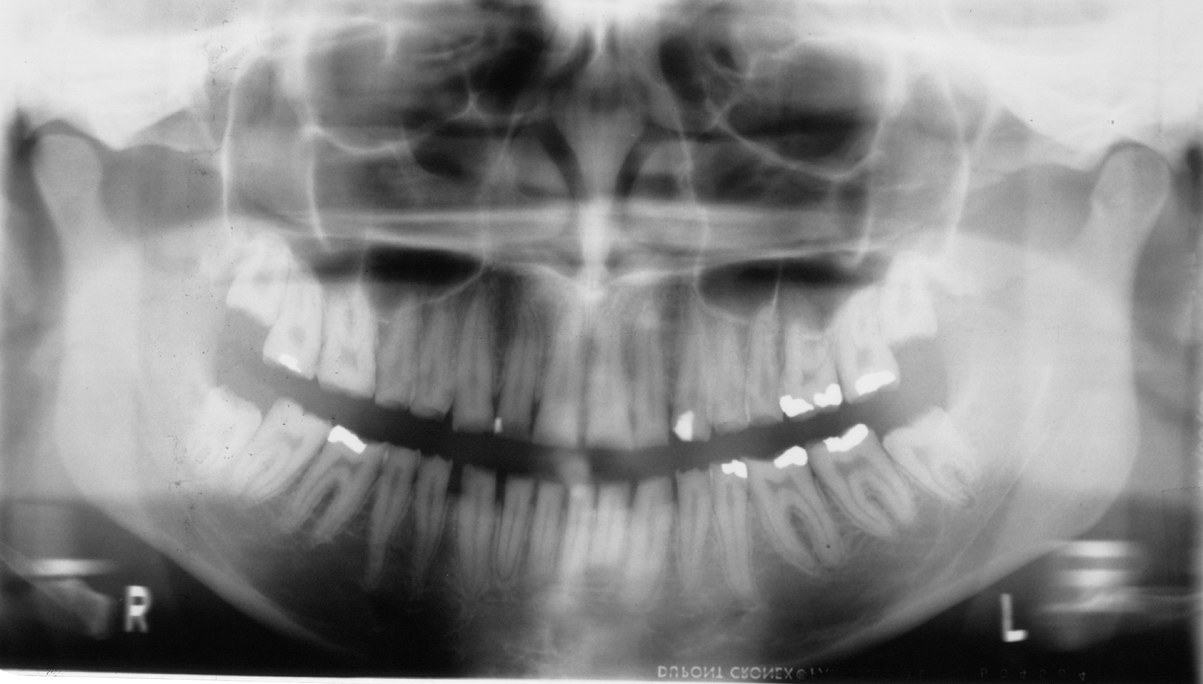

El Dr. Alfredo Natera, odontólogo, director del Centro Venezolano de Investigación Clínica para el Tratamiento de la Fluorosis y Defectos de Esmalte y docente de odontología operatoria en la Universidad Central de Venezuela (UCV), nos habla sobre la amelogénesis imperfecta.